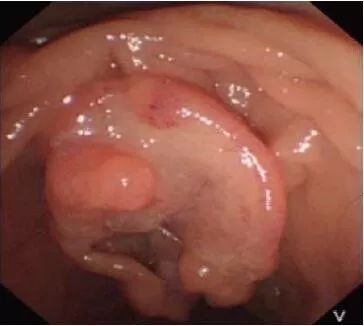

上腹部磁共振成像(MRI)检查结果显示,壶腹部异常信号结节,肝内外胆管、主胰管扩张,考虑肿瘤可能性大(图1)。十二指肠镜检查结果显示,主乳头呈菜花状肿块,病灶中央凹陷,外观充血、水肿,大小约3.0 cm×2.0 cm×2.0 cm(图2)。

图2 十二指肠镜下可见十二指肠乳头处有一约3.0 cm×2.0 cm×2.0 cm菜花状肿块,病灶中央凹陷,外观充血、水肿